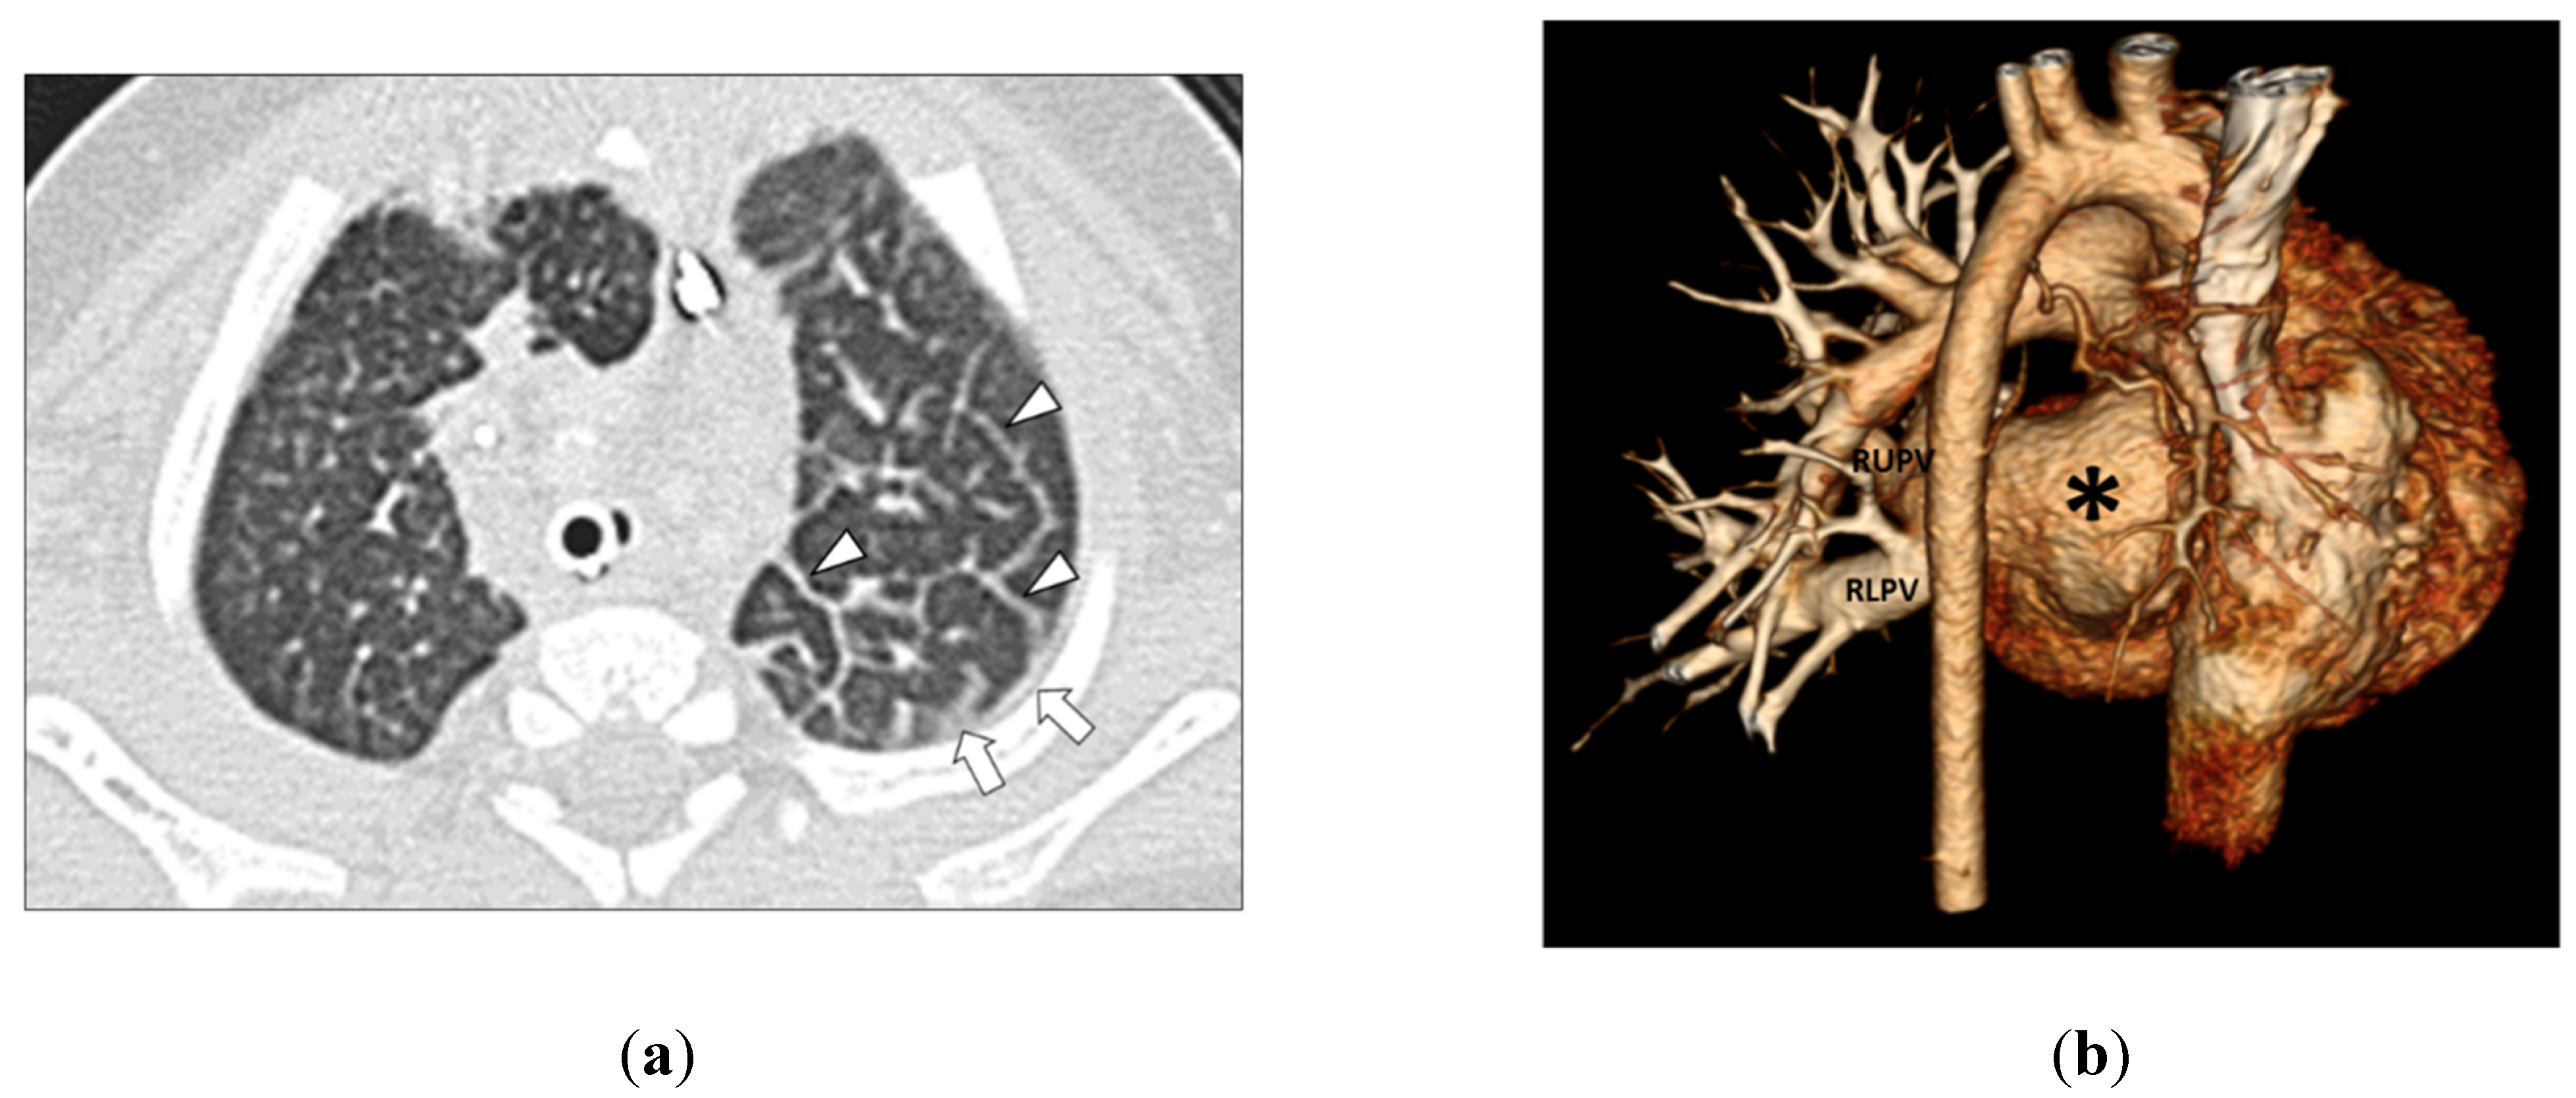

Figure 3. (a) 3-month-old girl with left-sided pulmonary vein stenosis but no history of aspiration. Axial lung window CT image shows left-sided septal thickening (arrowheads) and pleural thickening (arrows) in the left hemithorax. (b) 3-month-old girl with absent left pulmonary veins due to complete obstruction from severe pulmonary vein stenosis but no history of aspiration. The posterior view of the three-dimensional volume-rendered CT image of the vascular and heart strictures shows absent left pulmonary veins (asterisk). Normal and patent right upper pulmonary vein (RUPV) and right lower pulmonary vein (RLPV) are seen.

In Group 2 (PVS without aspiration), among 45 MDCT studies, four lung abnormalities were observed including GGO in 37 thoracic MDCT studies (82.2%), septal thickening in 36 thoracic MDCT studies (80.0%), consolidation in 3 thoracic MDCT studies (6.7%), and cyst in 1 thoracic MDCT study (2.2%) (Figure 3 and Figure 4).